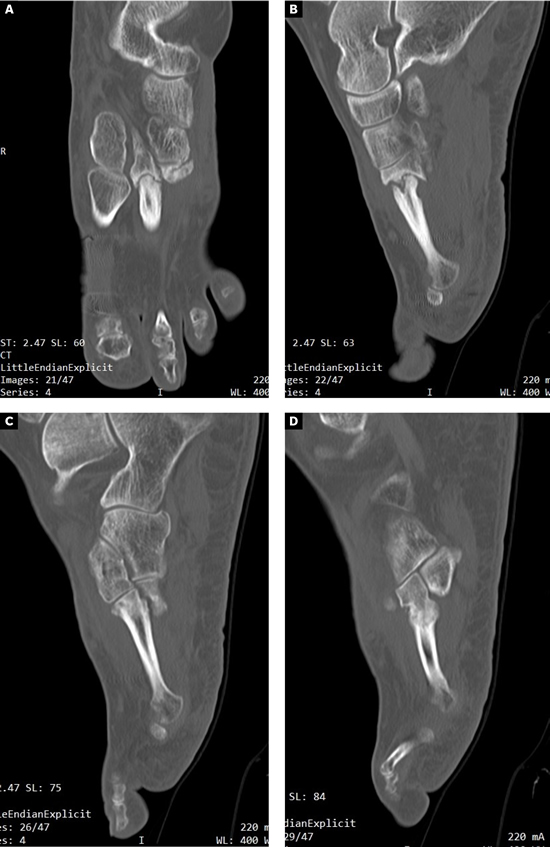

Se realizó radiografía dorso-plantar en carga del pie derecho (Figura 1) que mostraba una imagen radiológica compatible con ausencia de consolidación de las osteotomías en las bases de 2.º, 3.º y 4.º metatarsianos, además de la presencia de hallux abductus valgus. Se solicitó una tomografía axial computarizada (TAC) para estudiar más detenidamente el estado actual del proceso de consolidación ósea. La paciente acudió con resultado de TAC el 5 de mayo de 2015, donde se evidenció la ausencia completa de consolidación ósea en segundo metatarsiano (Figuras 2A y 2B), consolidación prácticamente completa de tercer metatarsiano (Figura 2C) y la presencia de callo óseo con consolidación incompleta en el cuatro metatarsiano (Figura 2D).

Figura 2. Radiografía dorso-plantar en carga del pie derecho. Se evidencia la ausencia de consolidación de las osteotomías en las bases de 2.º, 3.º y 4.º metatarsianos después de 9 meses de la intervención inicial.

El postoperatorio transcurrió sin incidencias y se realizaron curas postoperatorias con suero fisiológico y povidona yodada a los 7, 21 y 49 días postoperatorios. A las 6 semanas y 2 días (30 de julio de 2015) se realizó TAC de control que fue valorado el 7 de agosto de 2015 (7 semanas y 3 días tras la intervencion). Este TAC evidenciaba buena integración del injerto. Tras este hecho, junto con la favorable evolución clínica, se permitió a la paciente la carga parcial con bota tipo Walker durante 3 semanas para posteriormente comenzar a utilizar calzado convencional de forma progresiva.

A los 5 meses de la intervención se solicitó nuevamente un TAC comparativo que se realizó el 20 de noviembre de 2015 (Figura 6) que evidenció la integración completa del injerto y la consolidación del 4.º metatarsiano. La evolución clínica de la paciente fue muy positiva con ausencia completa de dolor realizando todas las actividades de la vida diaria con normalidad. Con fecha 25 de mayo de 2016 (11 meses postoperatorios) se realizó última visita de la paciente encontrándose esta en perfectas condiciones y dando el alta a la paciente. La paciente ha sido seguido posteriormente con revisiones anuales durante 4 años (hasta 2019) sin ninguna alteración.

Imagen 6. TAC postoperatorio a los 5 meses. 6A. Imagen del 2º metatarsiano que muestra integración del injerto con la placa dorsal. 6B. Imagen del 4º metatarsiano que muestra consolidación del 4º metatarsiano.